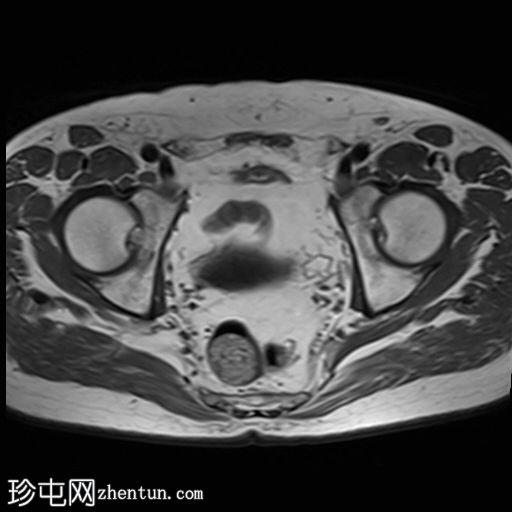

轴向位

T1时间

位于5点钟和6点钟位置之间,在STIR和T2加权图像上呈高信号。

瘘管起源于括约肌间平面附近,穿过肛门内外括约肌,并延伸至左侧坐骨肛门窝。瘘管内充满液体信号,周围有轻微水肿。肛提肌上方未观察到颅骨延伸。

根据圣詹姆斯大学医院的磁共振分类系统,该病例被归类为III级左侧肛周经括约肌瘘,左侧坐骨肛门窝可见炎症改变。